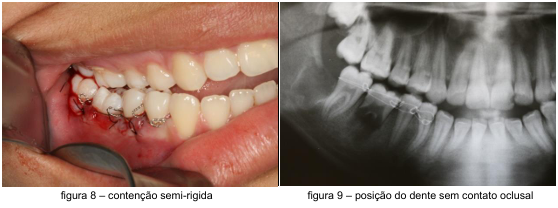

Após sutura do tecido foi feito contenção semi-rígida com fio ortodôntico n° 0 para fixação do elemento dentário no alvéolo, posicionado elemento transplantado abaixo da linha de oclusão para evitar traumas oclusais (figura 8 e 9).